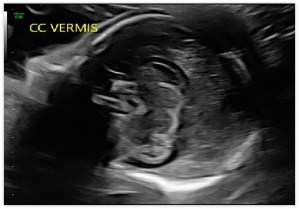

Cerebellar View

Above. The cerebellar view is axial oblique with rotation of the transducer from the thalamic view to the cerebellum, while obtaining a view of the central cerebellar echogenic vermis. This view allows visualization of the cerebellum and cisterna magna (posterior fossa).

Cerebellar Measurements

Above. The cisterna magna or posterior fossa measurement is taken as illustrated from the outer aspect of the cerebellar vermis to the internal side of the occipital bone, and is normally between 2 mm and 10 mm in depth. The transcerebellar diameter is also measured as illustrated from outer to outer aspect of the cerebellum and varies by gestational age. Note the box like cavum septi pellucidi (CSP) which can also be seen with the cerebellar view.